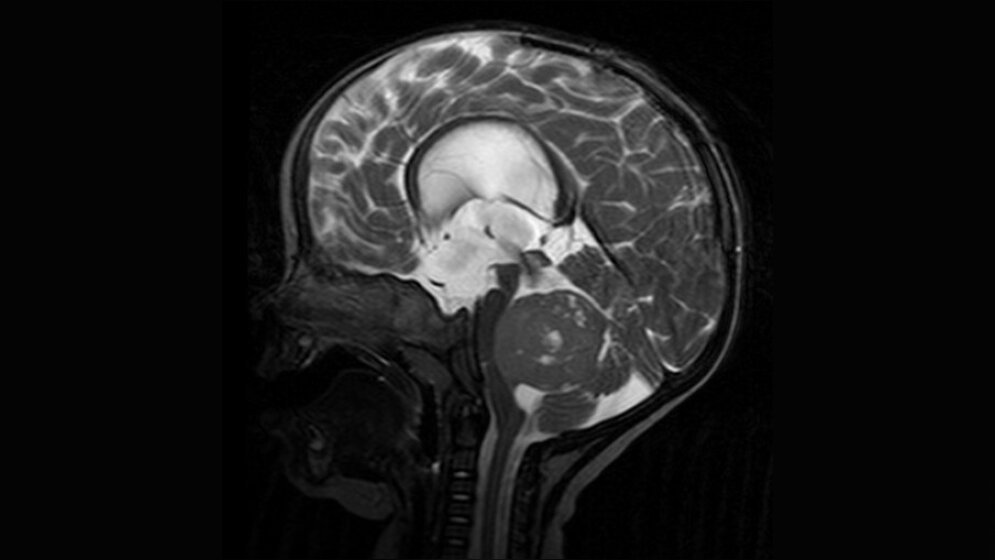

Medulloblastome sind seltene bösartige Tumoren des Kleinhirns, die vorwiegend bei Kindern vorkommen. Wissenschaftler gehen davon aus, dass in vielen Fällen erbliche Gendefekte die Entstehung dieser bösartigen Krebserkrankung auslösen. Standards für ein Routinescreening der Patienten nach solchen bekannten genetischen Faktoren oder gar Richtlinien und eine entsprechende flächendeckende Infrastruktur für die genetische Beratung betroffener Familien gibt es bisher allerdings nicht.